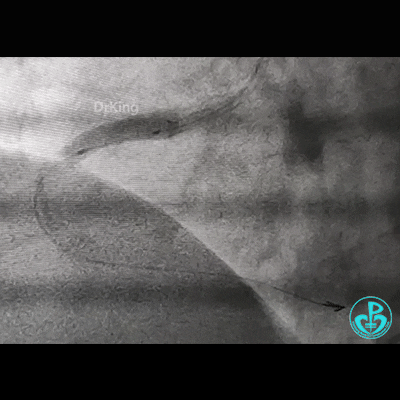

处理右冠,XB RCA,Sion、Sion blue导丝,2.0×20mm球囊。支架植入过程相当顺利,很快就完成,窃喜!心想后扩后马上结束!

植入3.5×29mm和3.5×24mm支架。

开始后扩,3.5×15mm后扩球囊不能进入近端支架口,GC系统飞出!故事开始。